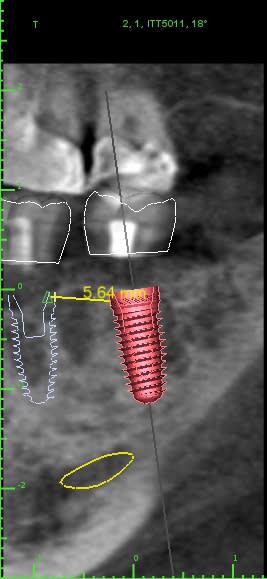

Petit update : Je me suis équipé chez Nobel (moteur + trousse chir + 10 Replace) et j'ai posé 3-4 cas en Nobel.

Et donc j'ai posé 3 Replant ce matin (le compatible Nobel Replace de chez ID) un RP11,5 (4,3x11,5) et 2 WP11,5 (5x11,5)

15 cross sections budgmt - Eugenol

3implants2 implant view dj28sl - Eugenol

Nobel clgpff - Eugenol

3implants0 implant view gz0ewo - Eugenol